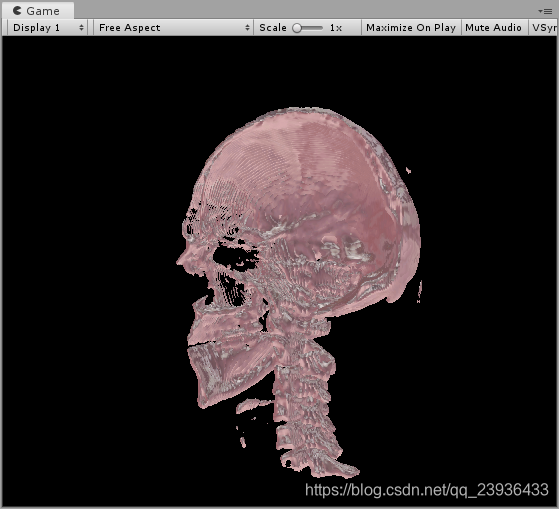

同理,如果我们想获得深层中的高密度的骨骼,我们就可以通过增大_Density值,同时增大_Contrast值使得密度差拉大,这样我们就可以显示出我们想要的高密度骨骼信息,

效果如下: